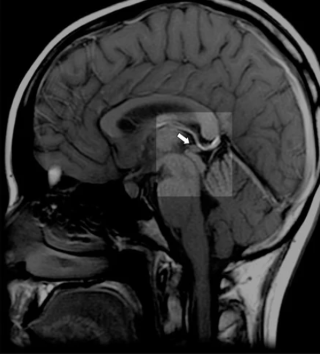

Deep in the geometric center of your brain, behind your eyes and between your ears, sits a pinecone-shaped gland no larger than a pea. The ancients called it the seat of the soul. Descartes declared it the principal seat of consciousness. Modern science calls it an endocrine gland.

The pineal gland is unique among brain structures — it exists outside the blood-brain barrier, making it exquisitely sensitive to everything flowing through your bloodstream. Under a microscope, pineal tissue contains rod-shaped, light-sensitive cells nearly identical to those in your retinas. Evolution didn't place retinal cells in the center of your skull by accident.

Here's what conventional medicine knows but rarely discusses: The pineal gland calcifies more than any other tissue in the human body. By middle age, many people's pineal glands contain calcium deposits visible on MRI scans, forming what researchers call "brain sand" or corpora araceacea.

Q: How do I know if my pineal gland is calcified?

A: Most people's pineal glands show some degree of calcification by middle age. Signs include: disrupted sleep patterns, difficulty achieving deep sleep, loss of dream recall, feeling disconnected from intuition, circadian rhythm disturbances (jet lag sensitivity, shift work intolerance), and early aging signs. An MRI or CT scan can show calcification directly, though most doctors don't routinely check for it.